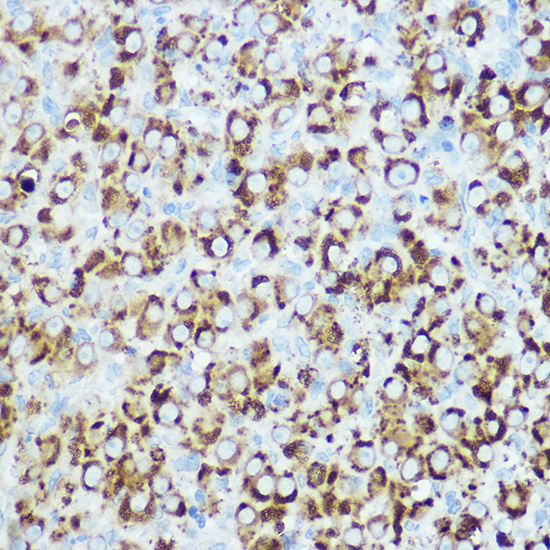

Immunohistochemistry of paraffin-embedded rat ovary using RSPO1 Rabbit pAb.

IHC 1:50 - 1:100